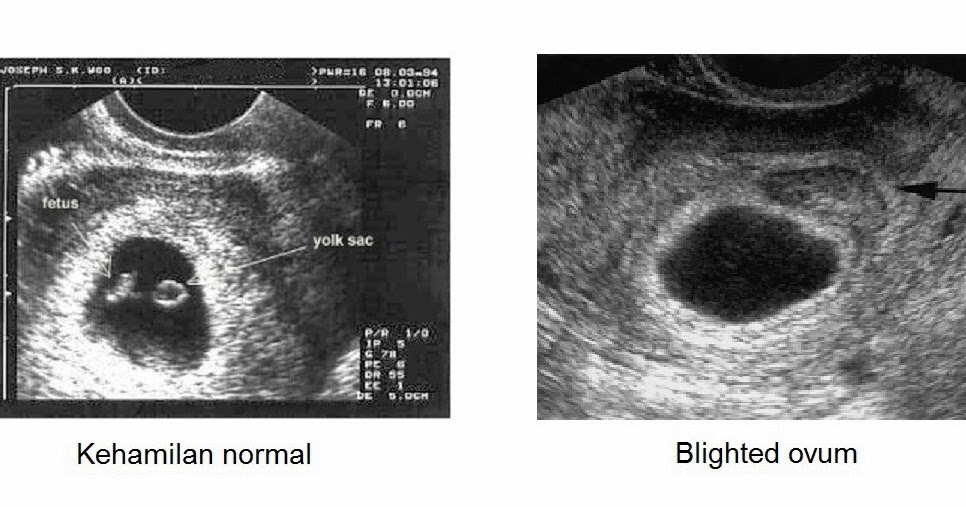

Anembryonic pregnancy is a form of early pregnancy failure, in which the developing, but the embryo is not formed. The term is synonymous with a blighted ovum is, but fell out of favor and should be avoided.

In pregnancy anembryonic, formed from the fertilized egg, but never developed, although histologically some fetal material can be shown in many cases.